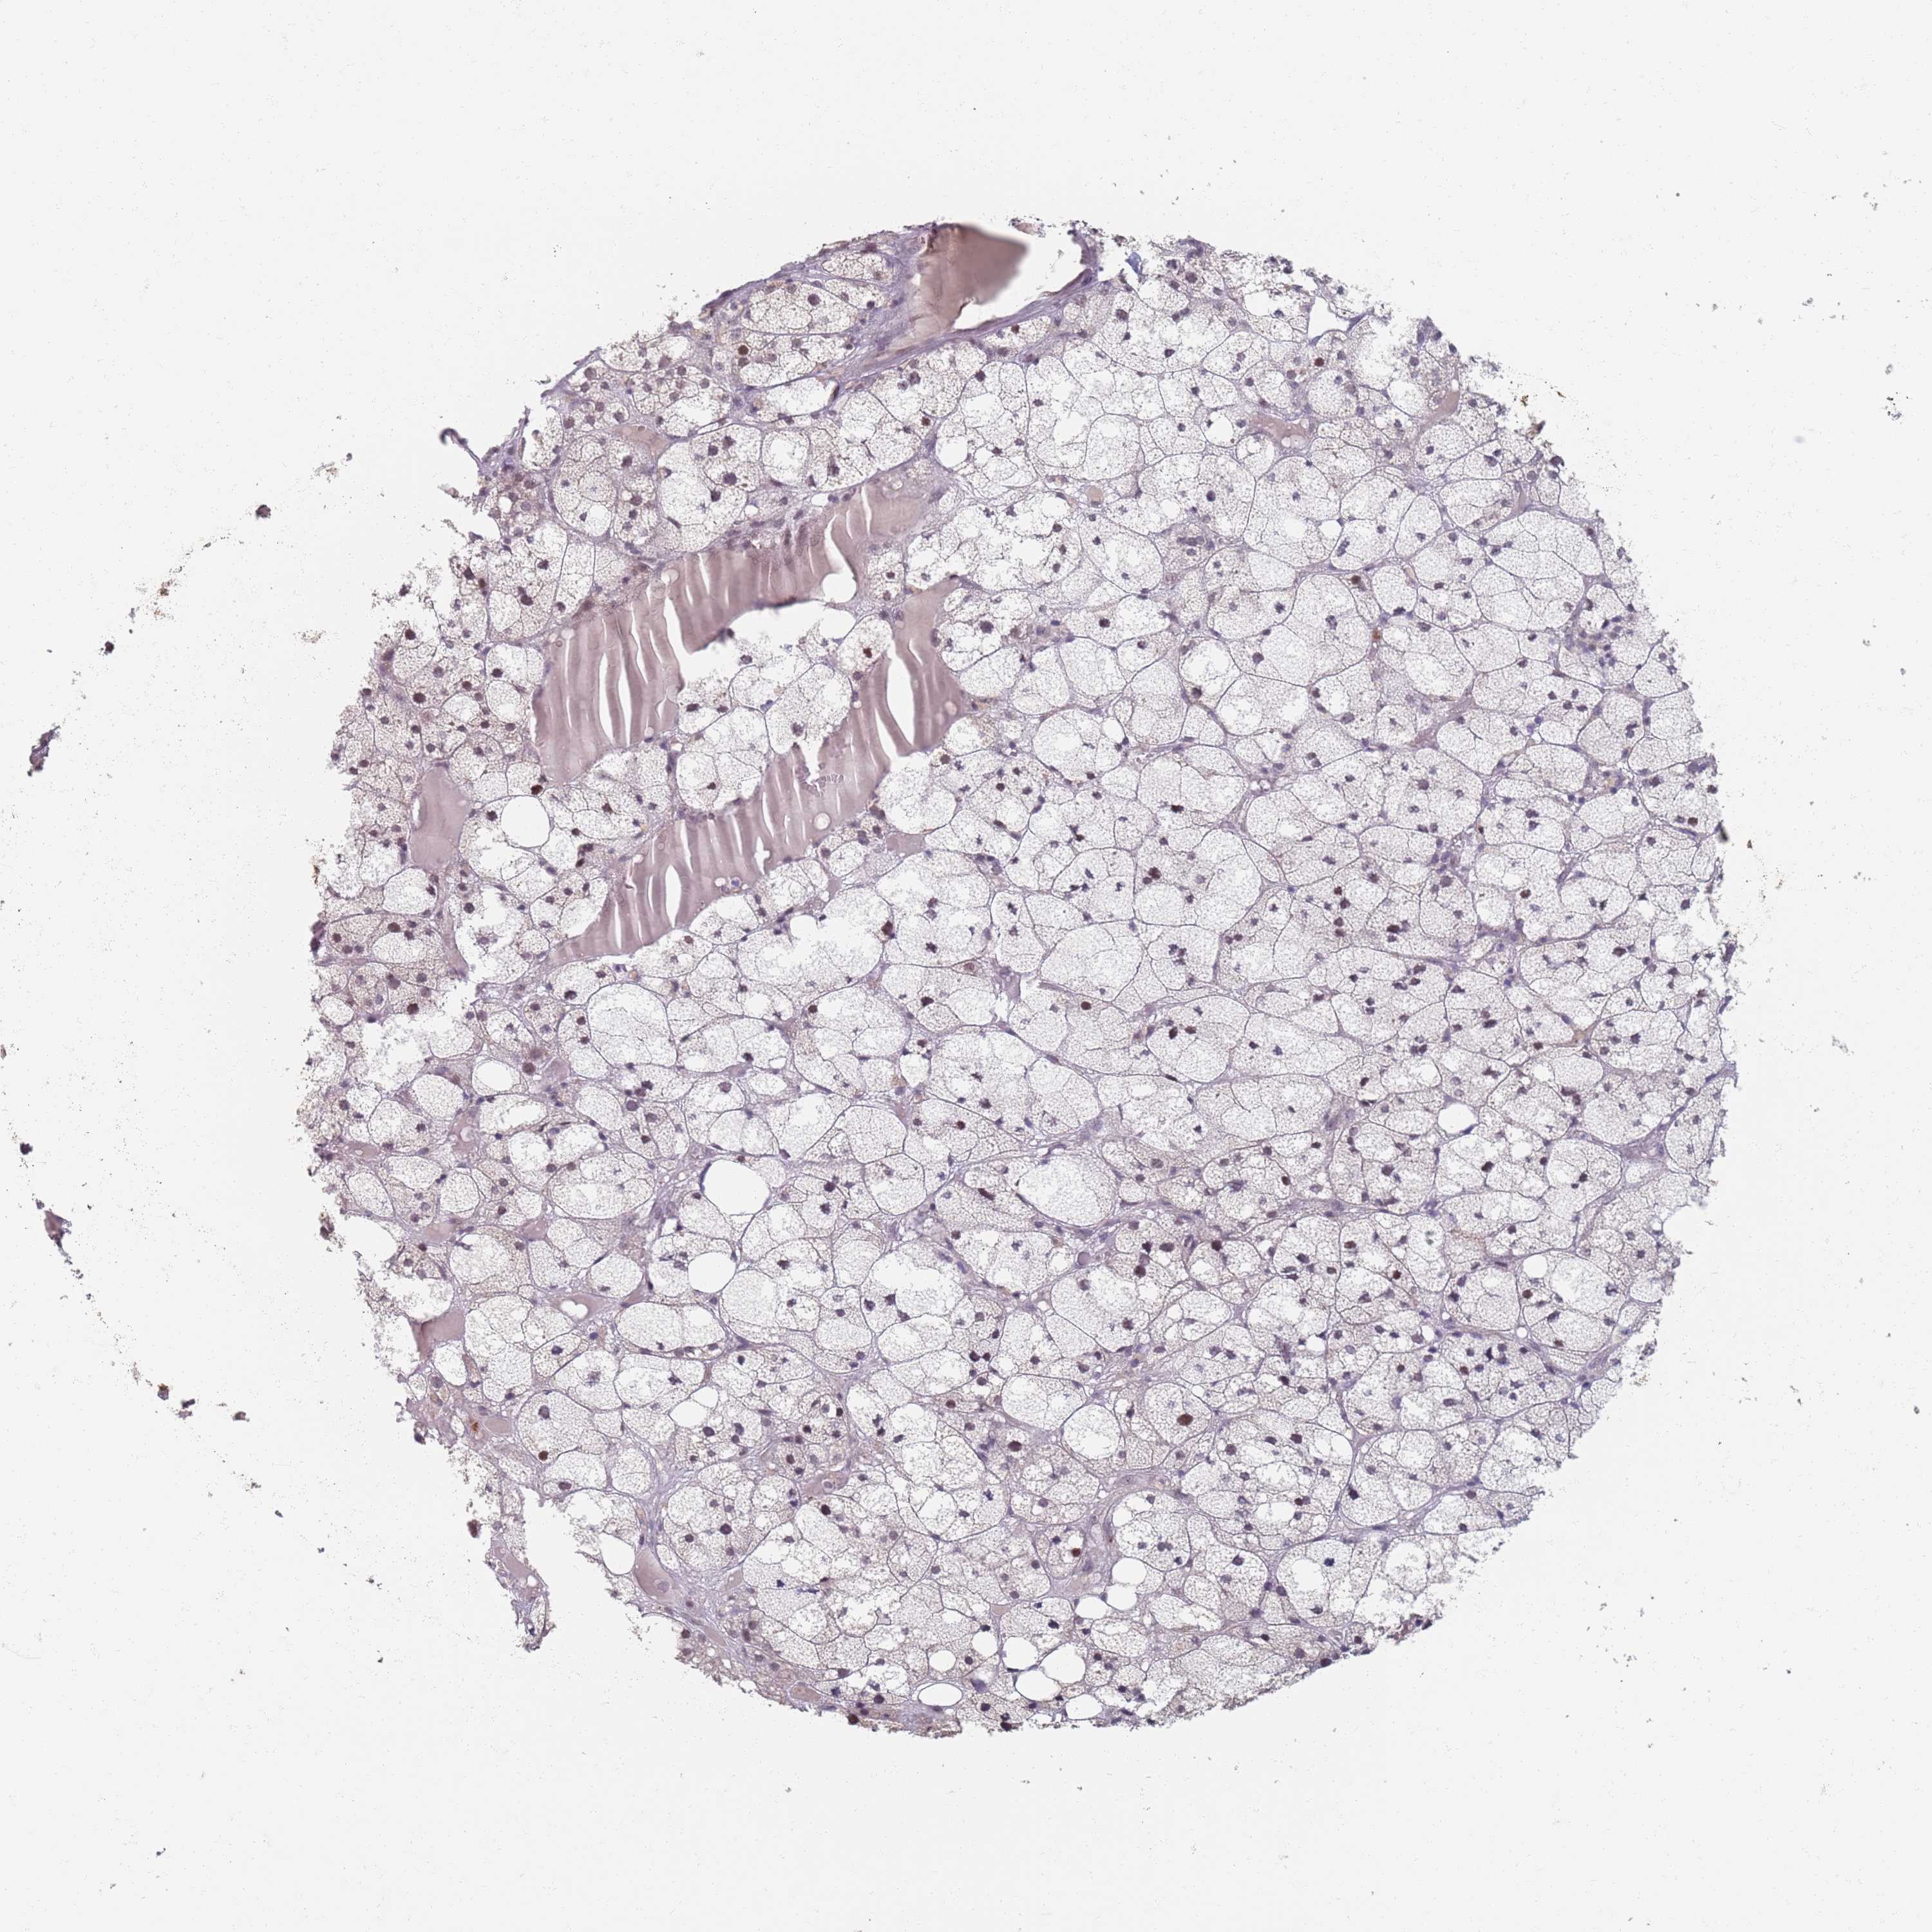

ADRENAL GLAND - Antibody stainingi

Antibody staining in the annotated cell types in the current human tissue is reported as not detected, low, medium, or high, based on conventional immunohistochemistry profiling in selected tissues. This score is based on the combination of the staining intensity and fraction of stained cells.

Each image is clickable and will lead to virtual microscopy that enables deeper exploration of all samples and also displays staining intensity scores, fraction scores and subcellular localization as well as patient and tissue information for each sample.

Antibody HPA049059

Glandular cells Low